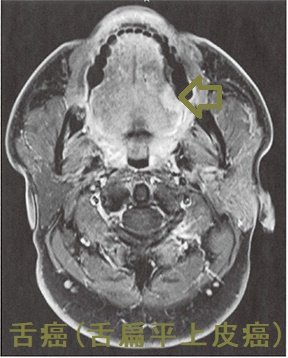

舌癌と甲状腺癌の重複癌

舌癌と甲状腺癌の重複癌の報告は比較的稀です。舌癌(扁平上皮癌)の顎下リンパ節転移に頸部郭清術を施行、郭清したリンパ節内に甲状腺乳頭癌の転移が発見されたそうです。(J.Jpn.Stomatol.Soc.43(1):46-50,January,1994)[J Oral Maxillofac Surg. 2018 Nov;76(11):2454.e1-2454.e6.]

舌癌(舌扁平上皮癌)MRI 脂肪抑制造影T1強調冠状断像